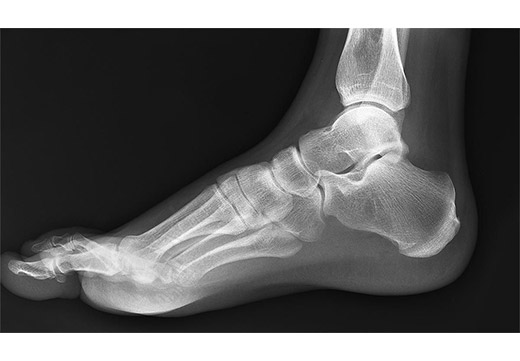

- Боковая – фотография делается в положении стоя, вторая нога на весу. Обязательно на пленке фиксируется голеностопное сочленение. Используется для выявления продольной формы изменения соотношения костных, мышечных структур, сухожилий.

Определить степень плоскостопия по снимку должен ортопед. Для этого пленку расчерчивают, фиксируя высоту свода стопы. На рентгеновской пленке выделяют треугольник, вершиной которого является верхняя часть первой плюсневой кости. Прочими контрольными точками являются выступающая часть пяточной кости, ладьевидно-клиновидный сустав.

Анализ изображений называется рентгеноморфометрия. В норме продольный угол стопы составляет 125–130 градусов, максимальная высота свода составляет 3,5 см, 1 и 5 головки плюсневых костей лежат на плоскости, остальные располагаются выше нормального положения сочленения.

При продольной форме врач будет измерять высоту и угол свода стопы. Степени отклонения от нормальных значений:

- Первая – деформация ноги отсутствует, угол свода – 131–140 градусов, высота – 2,5–3,5 см. Наблюдается нарушение плавности походки, повышенная усталость после бега, длительной ходьбы.

- Вторая – на снимках определяются проявления дегенеративных процессов в сочленениях. Угол свода – 141–155 градусов, высота – от 1,7 до 2,4 см. Наблюдается видимое изменение внешнего вида ступни.

- Третья – присутствует явная деформация костных структур, сочленений. Угол свода превышает 155 градусов, высота – менее 1,7 см. Наблюдается артралгии в коленных, тазобедренных суставах, позвоночном столбе. Ношение обычной обуви невозможно.